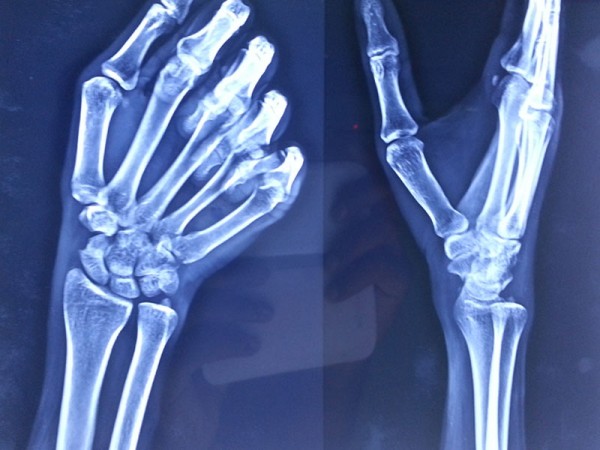

A case of scaphoid non-union

The young, male patient had the fracture of Rt scaphoid/ due to falling on an outstretched hand. The scaphoid fracture was treated, with the plaster cast for 1 ½ month elsewhere. Fracture of Rt Scaphoid was not united. This condition is called, the scaphoid non-union. It was treated with open reduction, and the iliac crest, bone grafting, and K wire stabilization.

3 months post surgery, patients Scaphoid was totally united and he is able to do all activities with his Rt Hand.

Before Surgery

After Surgery